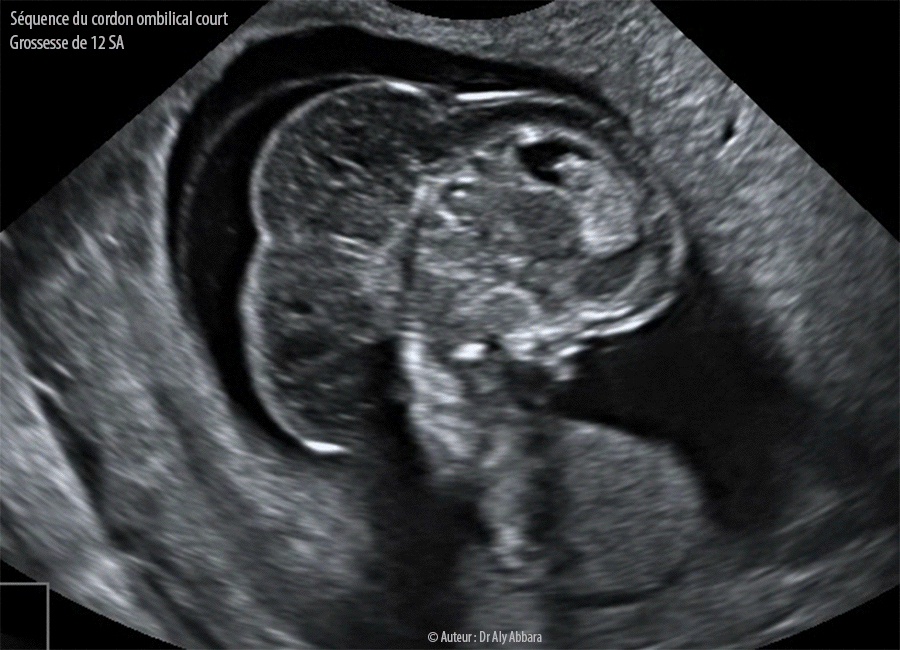

Séquence du cordon ombilical court :

Des extraits vidéo et un autodiaporama d'images échographiques d'un foetus polymalformé à 12 SA, il s'agit d'une " Séquence du cordon ombilical court " comportant : un énorme lymphangiome occipito-cervico-dorsal ; un thorax très étroit avec une ectocardie faisant partie d'une célosomie (cœlosomie) complète (à trois étages, supérieur, moyen et inférieur).

De son pôle inférieur, on peut remarquer la naissance d'un cordon ombilical extrêmement court (de quelques millimètres de longueur).

Le rachis paraît court et déformé (scoliose) avec l'absence totale de ses portions lombaire et sacro-coccygienne (régression caudale).

Une partie de la paroi thoracique postérieure adhère à surface fœtale du placenta rendant le foetus immobile (mouvements réduits et limités à son pôle céphalique).

Les extrémités supérieures ont été visualisées, par contre les membres inférieurs n'ont pas été identifiés, car absents.

Le caryotype fœtal n'a pas été étudié. La grossesse s'est terminée par un avortement spontané.